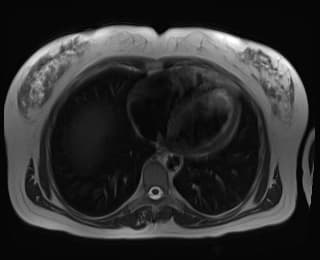

Axial C+ arterial phase

Một khối lớn, giới hạn rõ (well-circumscribed), dạng thùy (lobulated) xuất phát từ mặt dưới phân đoạn III thùy gan trái, kích thước 15 cm x 9,5 cm x 13,2 cm.

Khối này cho thấy tăng quang (enhancement) không đồng nhất (heterogeneous) ở thì động mạch, với hiện tượng washout tương đối ở thì tĩnh mạch cửa và thì muộn.

Trong khối có thành phần dạng nang (cystic component).

Một vùng tăng tỷ trọng không đồng nhất (heterogenous hyperdense) khu trú lớn nằm ở phần bên phải, phía dưới của khối, phù hợp với khối máu tụ (hematoma).

Dấu hiệu claw sign được quan sát rõ, đặc biệt trên các mặt phẳng coronal và sagittal.

Dịch tự do mật độ nhẹ trong ổ bụng vùng chậu, phù hợp với tràn máu ổ bụng mức độ nhẹ (mild hemoperitoneum).

Một trường hợp lâm sàng với triệu chứng đau bụng trên dữ dội, đột ngột, hình ảnh cho thấy khối lồi ra ngoài (exophytic) lớn ở thùy gan trái, được chứng minh bằng bệnh phẩm là u tuyến gan vỡ (ruptured hepatic adenoma).

U tuyến gan vỡ (ruptured hepatic adenoma)